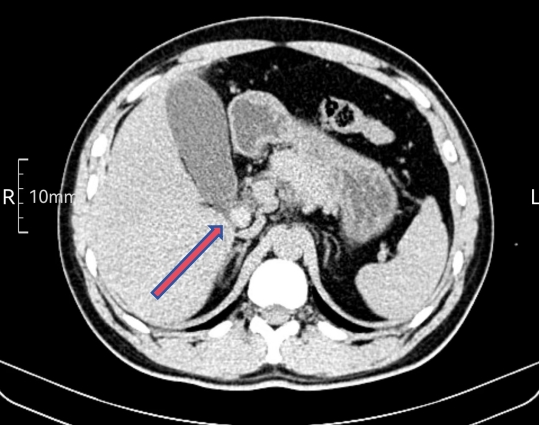

胆囊结石掉进胆总管形成胆总管结石

②大结石(以2cm为例):长期刺激胆囊壁,胆囊反复炎症,可能增加胆囊癌的风险。各类结石还可能会造成胆囊颈部嵌顿,阻塞胆囊管,导致胆囊积液、胆囊炎症加重,甚至出现化脓、坏疽、穿孔等。

结石嵌顿于胆囊颈部

结石嵌顿导致胆囊化脓、坏疽